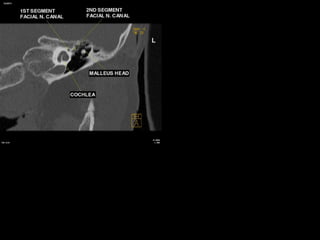

Segments

 intracranial (cisternal) segment - zero branches

 meatal (canalicular) segment (internal auditory canal): 8 mm long, zero branches

 labyrinthine segment (IAC to geniculate ganglion): 3-4 mm long, 3 branches

(from geniculate ganglion)

 tympanic segment (from geniculate ganglion to pyramidal eminence): 8-11 mm

long, zero branches

 mastoid segment (from pyramidal eminence to stylomastoid foramen): 8-14 mm long, 3

branches

 extratemporal segment (from stylomastoid foramen to division into major branches): 15-

20 mm, 9 branches

b) The Mesotympanum :

Three ossicles in the mesotympanum transmit

sound waves from the tympanic membrane to

the oval window in the vestibule :

1-Malleus ((head, neck, anterior process, lateral

process, and manubrium)

2-Incus (body, short process, long process, and

lenticular process)

3-Stapes (head/capitellum, anterior crus, posterior

crus, and footplate )